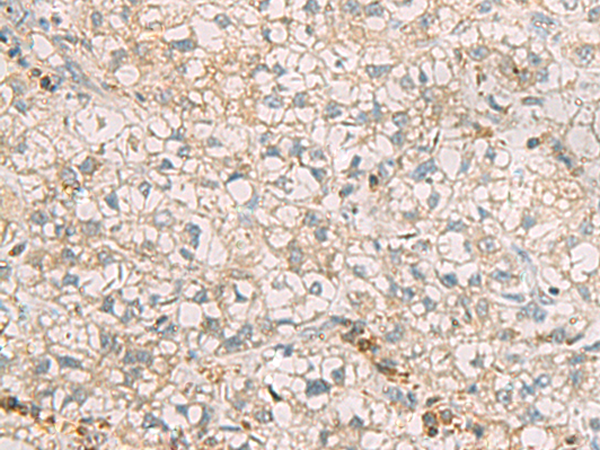

分类: 科研抗体货号: P03226别名: INI; Rds3; SF3B7; SAP14b; SF3b14b; bK223H9.2应用: WB,IHC反应种属: Human, Mouse, Rat